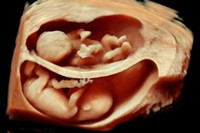

懷孕三個(gè)月胎兒長(zhǎng)成什么樣子呢?想必這是準(zhǔn)媽媽們想要迫徹知道的答案吧。自從準(zhǔn)媽媽成功受孕以來,胎兒寶寶在肚子里靜靜的呆著,先是給準(zhǔn)媽媽們帶來一些妊娠不適的反應(yīng),...

懷胎進(jìn)入四個(gè)月時(shí),一切都在慢慢進(jìn)入穩(wěn)定狀態(tài)。此時(shí)的準(zhǔn)媽媽們已經(jīng)擺脫了孕吐的煩惱,胃口也在逐漸的恢復(fù)當(dāng)中。所以,趁這個(gè)時(shí)候準(zhǔn)媽媽們要注意飲食上的補(bǔ)充,把之前因?yàn)樵型?..

懷孕5個(gè)月胎兒圖什么樣子呢?關(guān)于胎兒的發(fā)育圖,正是準(zhǔn)媽媽們關(guān)心的熱門話題之一,在整個(gè)孕期胎兒寶寶的發(fā)育狀況,發(fā)育速度,健康狀態(tài),胎兒性別,這些都是準(zhǔn)媽媽們最關(guān)心和在...